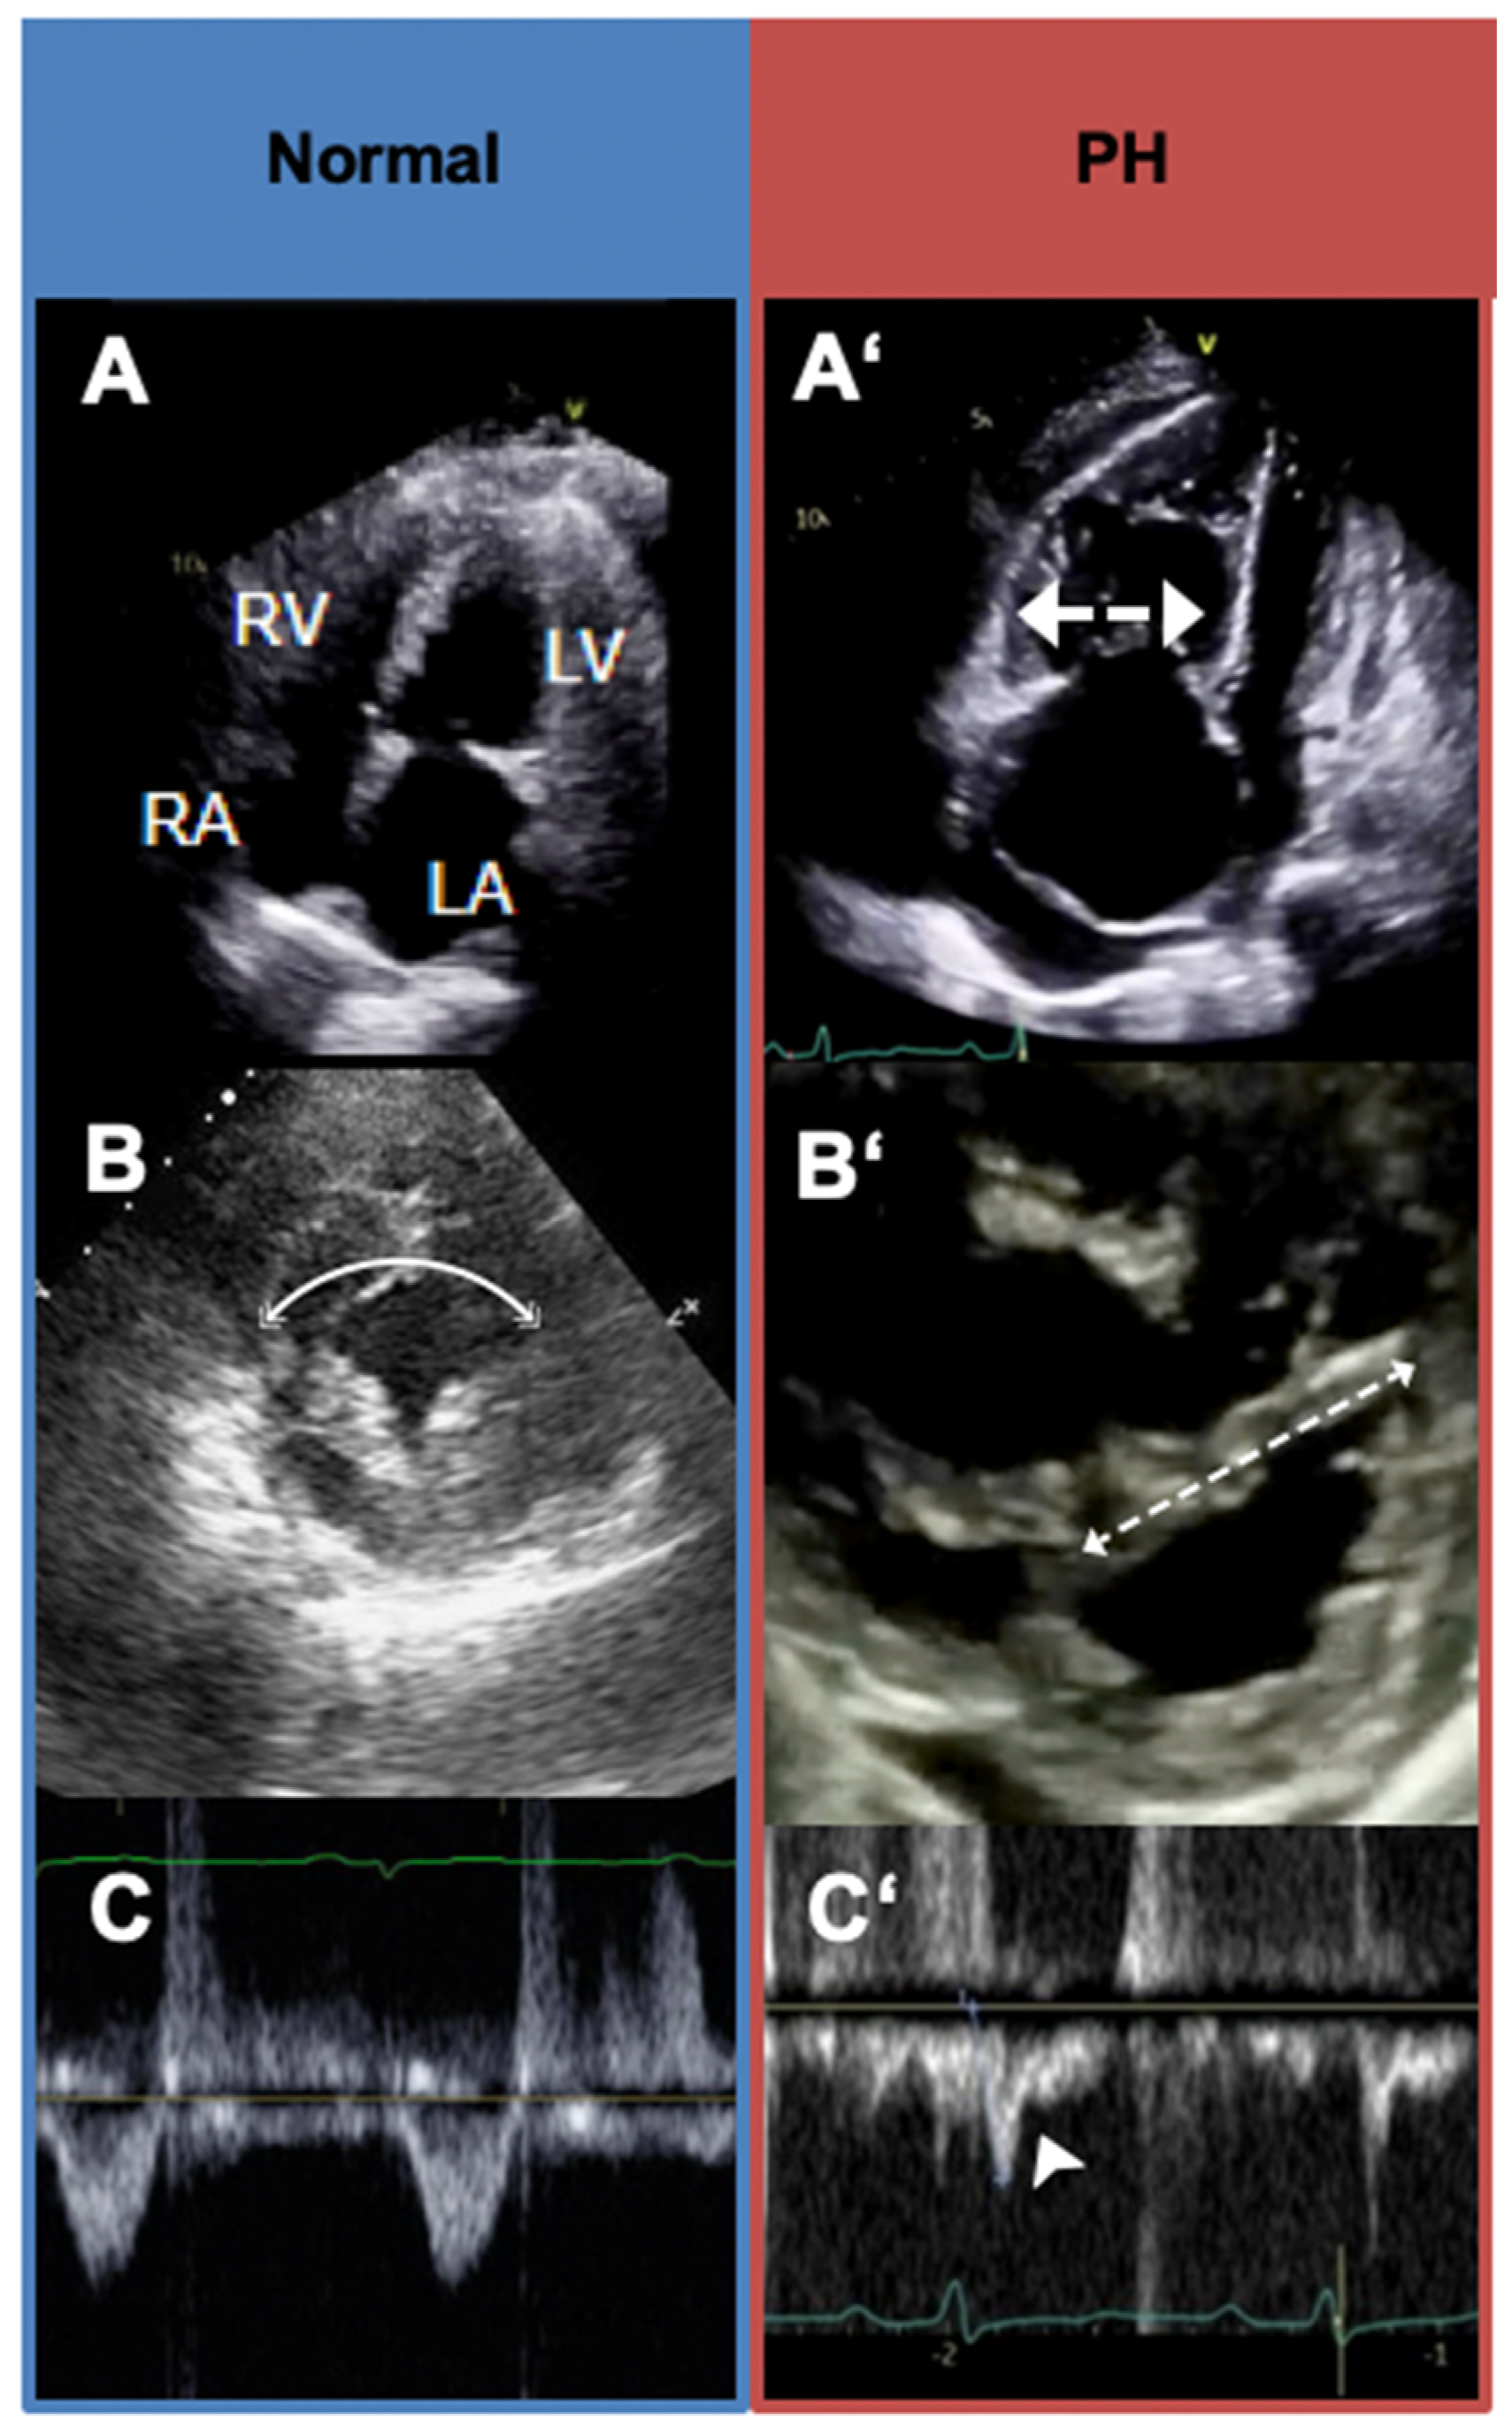

5.3. Transthoracic Echocardiography

| TTE [17] | 83% | 72% | Useful initial noninvasive modality for screening and measurement of pulmonary pressures. | Dependence on the quality of imaging, difficulty in image acquisition with increased RV volumes, steady heart rate, and experience of the laboratory staff. |